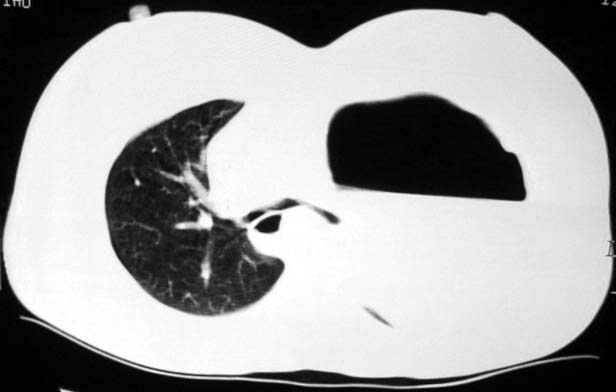

标题: CT5517:女性、24岁,反复胸痛、气促不能平卧半月。 [打印本页]

标题: CT5517:女性、24岁,反复胸痛、气促不能平卧半月。

左肺可见二个含气或液气的囊状影,左肺段支气管、左肺动脉显示不清,纵隔右移,考虑:左肺支气管肺囊肿,左肺发育不良,纵隔疝。

左侧气液腔与胃腔影相连,考虑膈疝。钡餐检查有助于诊断。

我看这是膈疝,在纵隔窗第六\\七幅图像上可见胃粘膜影,再者可见两个腔影,这在液气胸是不会有的.

支持膈疝,纵隔窗内可见消化道的内容物。

“反复胸痛、气促不能平卧半月”。+影像学表现=膈疝

液气胸 怎么会有2 个大腔?

还是个膈疝